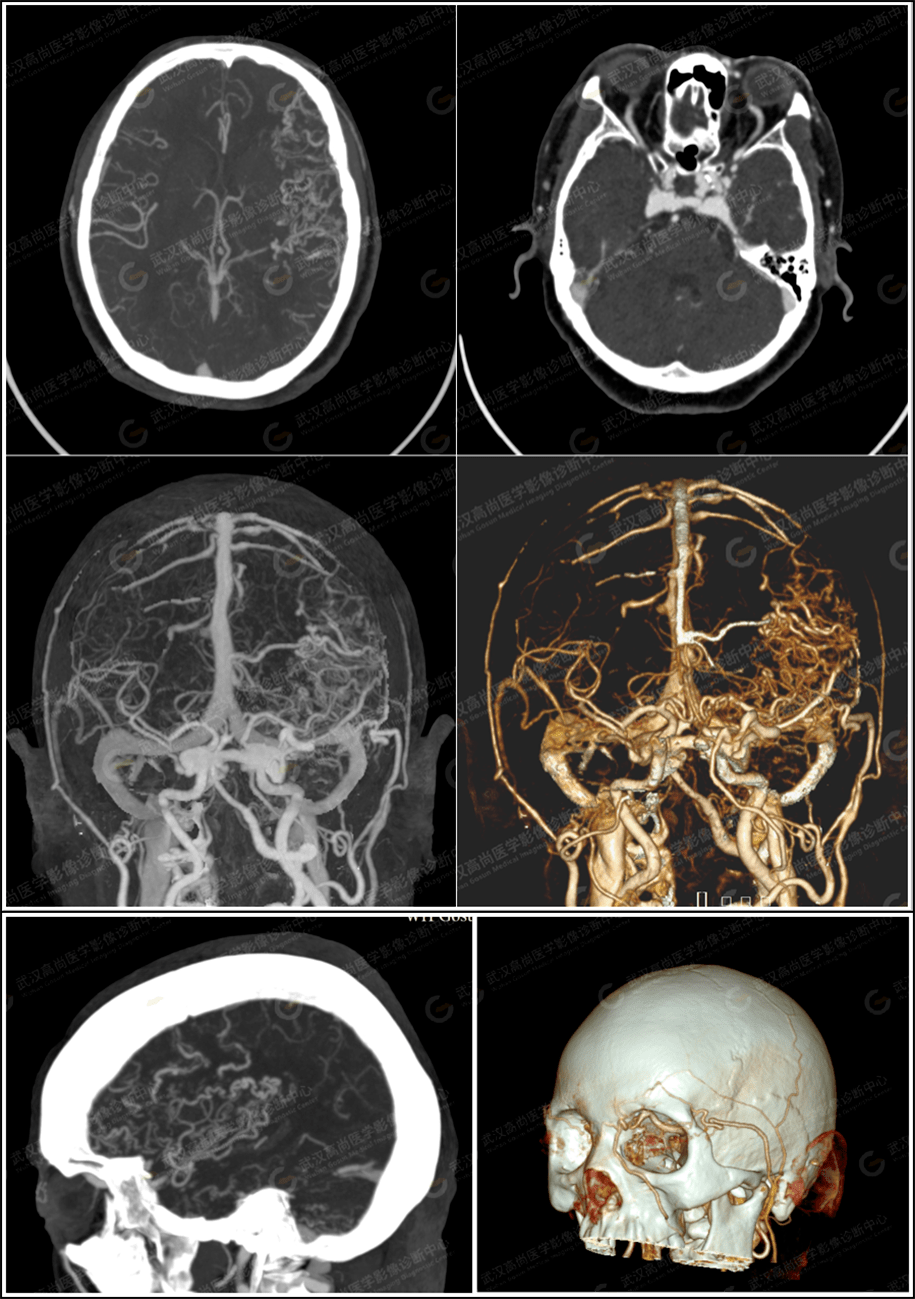

【高尚病例】头颅cta发现脑动静脉畸形1例【成都高尚医学】_手术_血管

仔细阅片cta未见明显引流静脉,考虑右侧脑膜中动脉假性动脉瘤可能更大